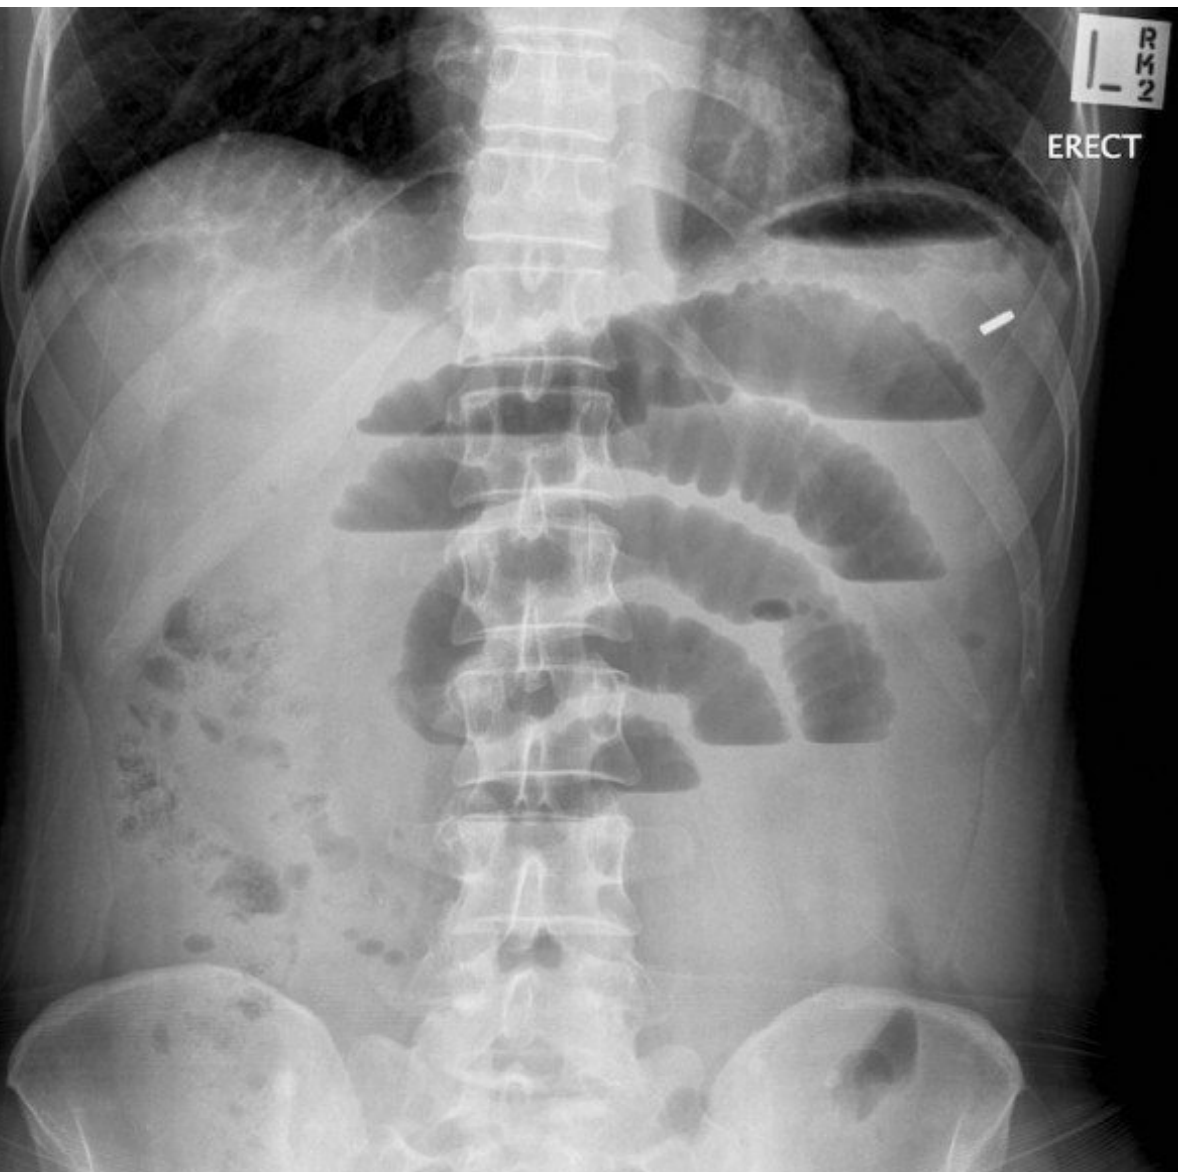

Q

Diagnosis?

Why?

SBO

1. dilated loops of bowel

2. multiple fluid levels

3. small bowel - central/3mm/valvular coneventes